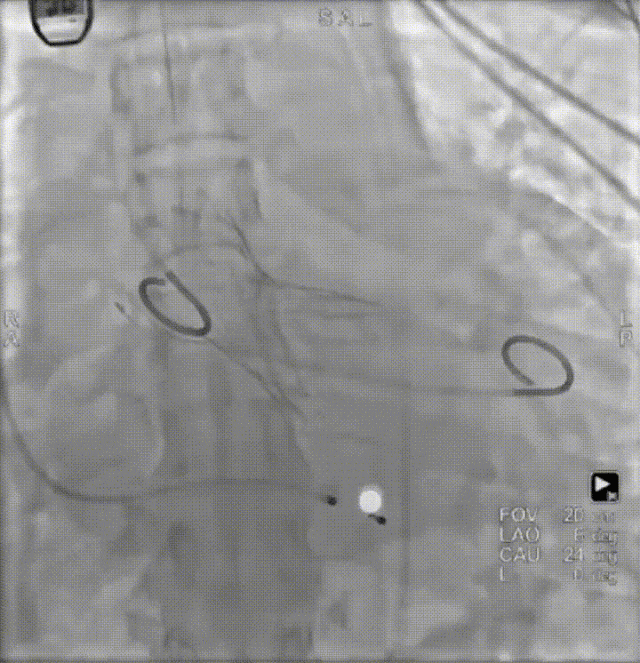

患者病史 男性,74y, 因 “发现心脏瓣膜病 1 年,加重伴喘气半年” 入院。门诊检查显示主动脉瓣重度AS并伴轻-中度AR。患者基础疾病较多:胸腹主动脉多发穿透性溃疡、心功能III级等,手术指征明确,但风险极高。 术前CT LVOT- Annulus 倒梯形,对植入瓣膜有挤压位移风险,Annulus直径23.7mm,瓣叶增厚,钙化集中在无冠窦边缘。 左冠脉开口高度可,瓣叶不长、窦部空间较大,无冠脉风险;室间隔膜部较短,有一定PPI风险,心脏角度37.9°;心室较小,有一定循环崩溃风险,术前注意补液。 术前造影角度及入路:血管入路散在钙化、无迂曲;主动脉弓条件好、双侧股动脉直径大、右股穿刺点侧壁存在环形钙化 左右重合位:RAO 7° CAU 21° 右窦中心位:LAO2 1° CAU 1° 手术策略 20mm球囊预扩后植入AV26瓣膜,同时做好预防循环崩溃、传导阻滞的应急预案。 术中挑战 1)球囊预扩:20mm球囊预扩时无明显 “腰征”,但存在少量反流,提示瓣膜钙化与解剖结构对扩张的阻力不均 2)首次释放偏差:第一次定位释放时,瓣膜在 “开花” 过程中下滑约 3mm,工作位观察显示小弯侧瓣周漏较多(深度超过完全覆膜区),需二次调整。 3)二次精准定位:以猪尾导管为参照,将定位点调整至 “猪尾 - 2mm” 处,结合真实窦底深度(较深)重新释放,最终瓣膜位置稳定,瓣周漏显著减少。 术后即刻效果: 瓣膜形态良好,跨瓣压差从术前的 67mmHg 降至 6mmHg,且无明显瓣周漏,冠脉开口通畅; Commisural Alignment 术后即刻超声: Prostyle A®预装干瓣——助力临床最优化解决方案: √ 平衡的径向支撑力:特殊的解剖结构下位置形态良好,术后跨瓣压差大幅降低,血流动力学改善明显; √ 80%可回收设计:支持术中二次调整释放位置,保证精准释放; √ 平衡的收腰设计&Commissural Alignment设计: 为患者后期冠脉PCI保留了生命通道;